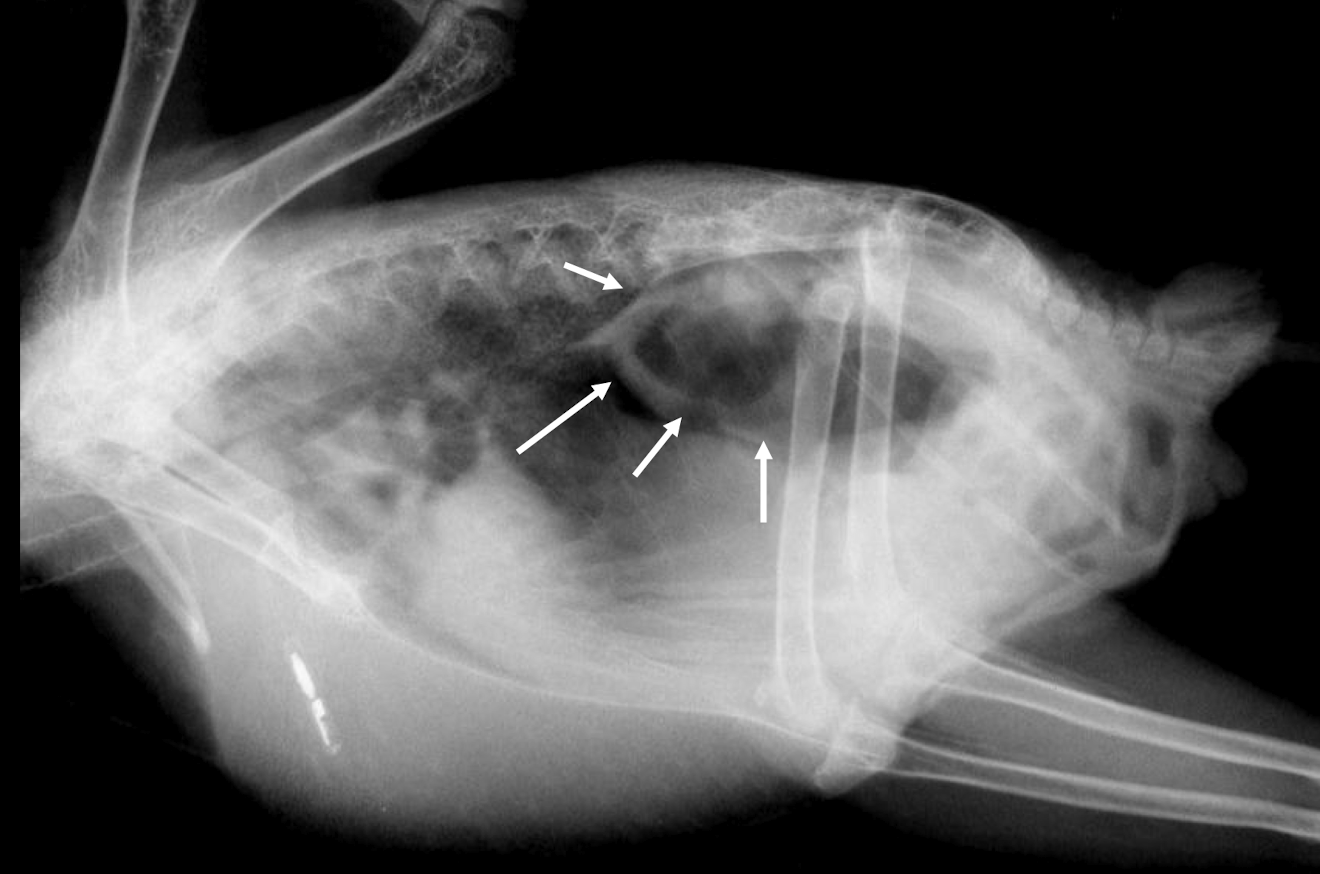

Whats wrong?

Fungal airsacculitis